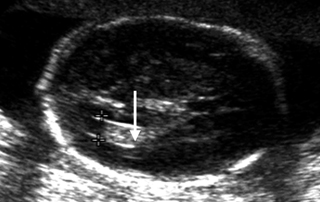

Γ. Διακοιλιακή απεικόνιση

1. Μέτρηση διαμέτρου πλαγίων κοιλιών (φ.τ. <10mm): Διάταση βρίσκεται σε υδροκεφαλία, σε γενετικά σύνδρομα και σε τρισωμία 21.(10,15,23)

2. Απεικόνιση χοριοειδούς πλέγματος εντός των πλαγίων κοιλιών. Αναδύεται από το έσω τοίχωμα της κοιλίας.

3. Εντόπιση κύστεων στα χοριοειδή πλέγματα ετερο/αμφοτερόπλευρα. Υπάρχει μικρή συσχέτιση με τρισωμία 18.(15,42)

- Διάταση πλάγιων κοιλιών εγκεφάλου, με τα χοριοειδή πλέγματα να αιωρούνται χαρακτηριστικά εντός τους.

- Περίμετρος κεφαλής συνήθως μικρότερη ή φυσιολογική σε σχέση με την ηλικία κύησης πριν την 24ηεβδ. Αντίθετα, είναι μεγαλύτερη όταν το αίτιο αφορά απόφραξη.

- Το πηλίκο των πρόσθιων ή και των οπίσθιων κεράτων των πλάγιων κοιλιών προς το αντίστοιχο ημισφαίριο είναι >95ης θέσης των φυσιολογικών τιμών.(19,23)